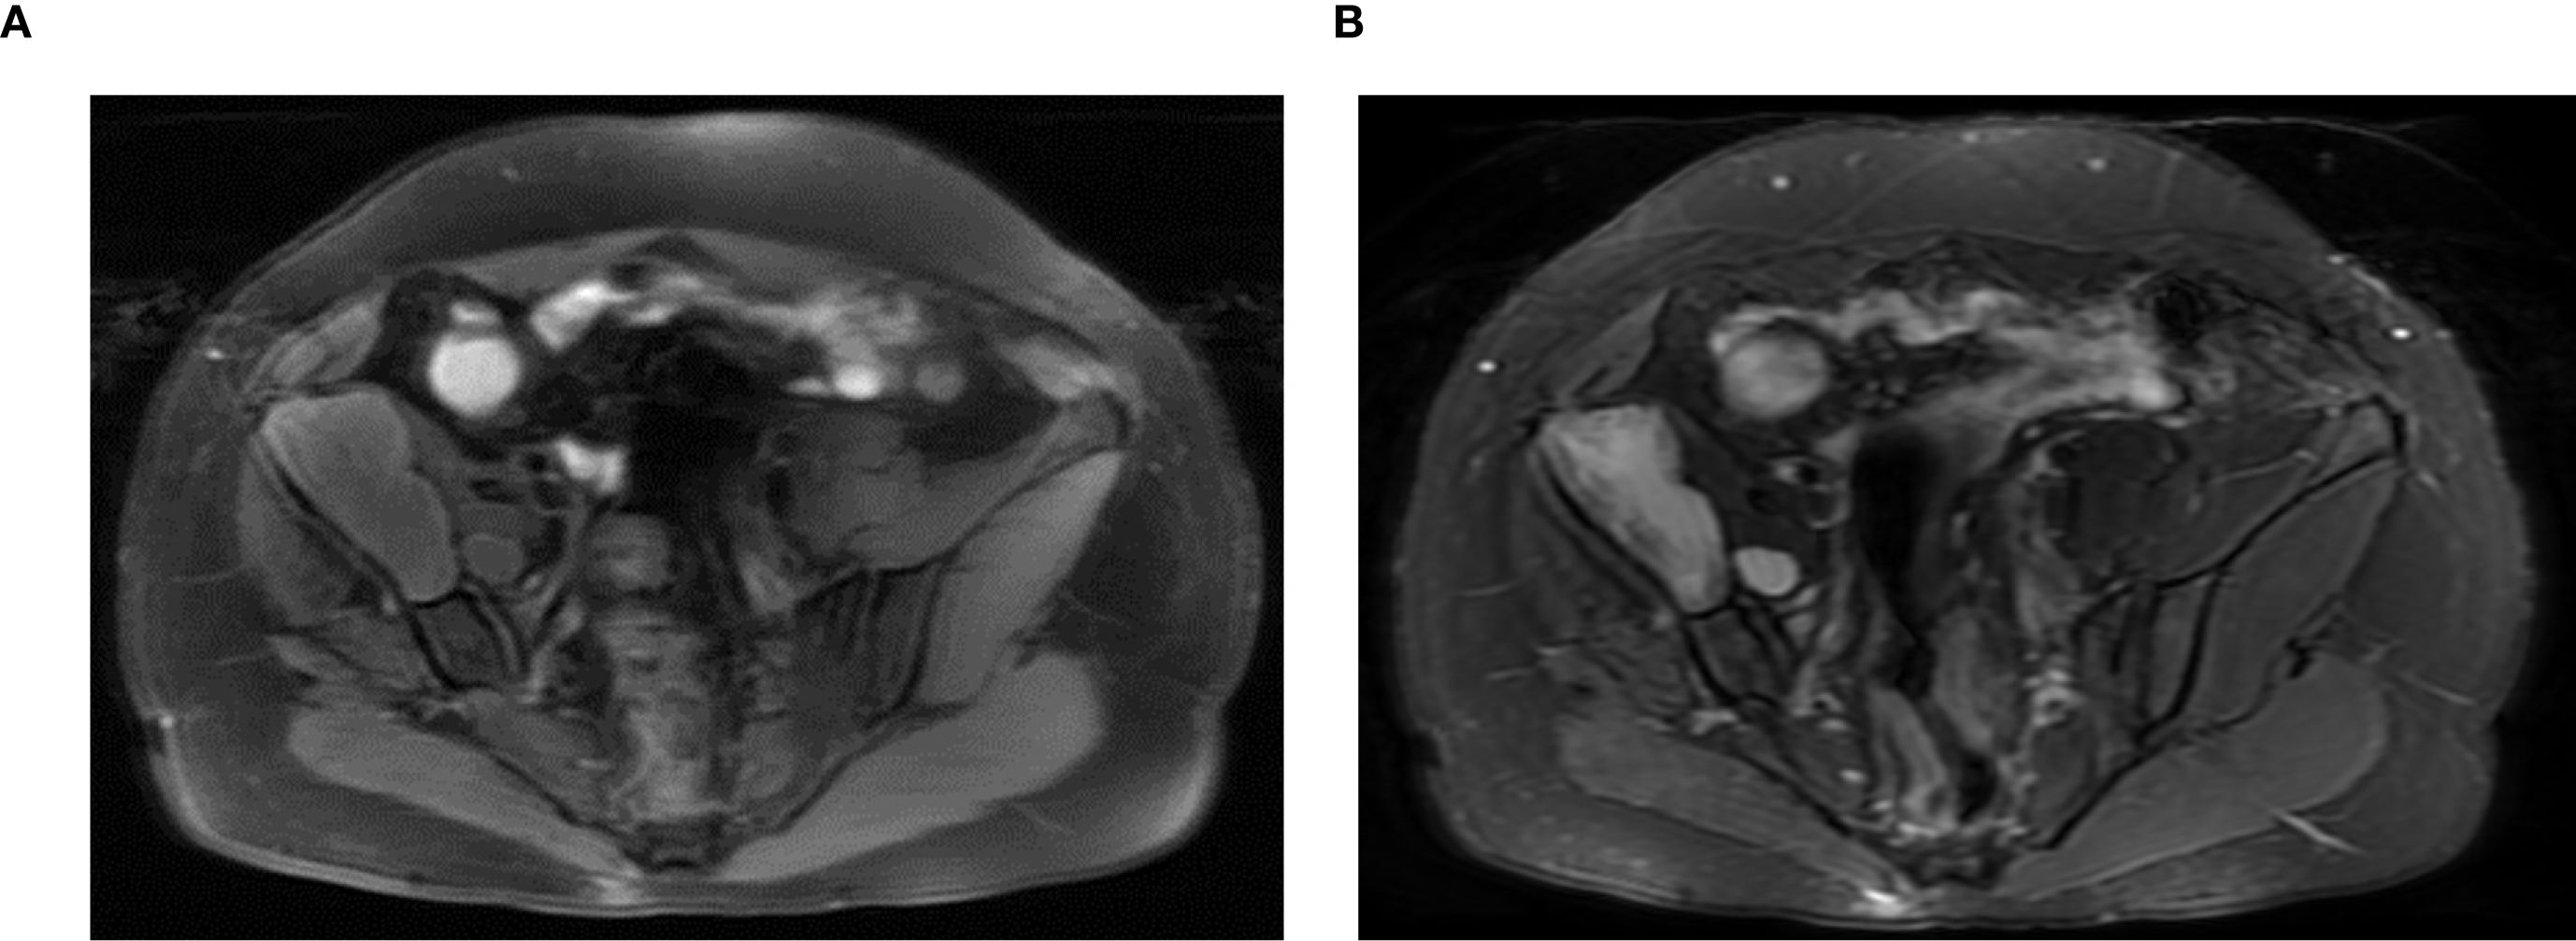

Laboratory examinations revealed no significant abnormalities. The pelvic plain film showed that the joint space of the right hip joint was narrowed, the femoral neck was shortened, and there was ischemic necrosis of the femoral head. Radiographs revealed a large expansile radiolucent lesion, with cortical erosion of the right iliac bone (Figure 1). Computed tomography (CT) revealed significant osteolytic destruction in the right iliac wing, along with a mass in the surrounding tissue. Irregular cystic degeneration areas were observed within it. The mass, measuring approximately 10.3 cm × 6.2 cm × 7.8 cm, had an indistinct boundary with muscle tissue (Figure 2). Magnetic resonance imaging (MRI) revealed an iliac mass showing hypo intensity.

on the T1-weighted and hyper intensity on the T2-weighted images (Figure 3). Diffusion-weighted imaging and apparent diffusion coefficient map showed diffusion restriction of the lesion. MRI findings of diffusion restriction without any enhancement favored the diagnosis of an epidermoid cyst. In view of the progressive trend of the symptoms, the relatively large volume of the mass, the ineffectiveness of conservative treatment, and the quite convincing results of imaging examinations, we recommended giving priority to the surgical removal of the mass at that time, and then performing hip replacement surgery at an appropriate time later. The patient agreed to the surgical intervention and consented to the use of her own imaging and pathological studies for educational purposes.

Two MRI scans labeled A and B show cross-sectional images of the abdominal area. Both images display various internal structures, including organs and soft tissues, with differing levels of brightness and contrast, possibly highlighting different tissue types or abnormalities for medical analysis.

Figure 3. Magnetic resonance imaging (MRI) revealed an iliac mass showing hypo intensity on the T1-weighted (A) and hyper intensity on the T2-weighted images (B).